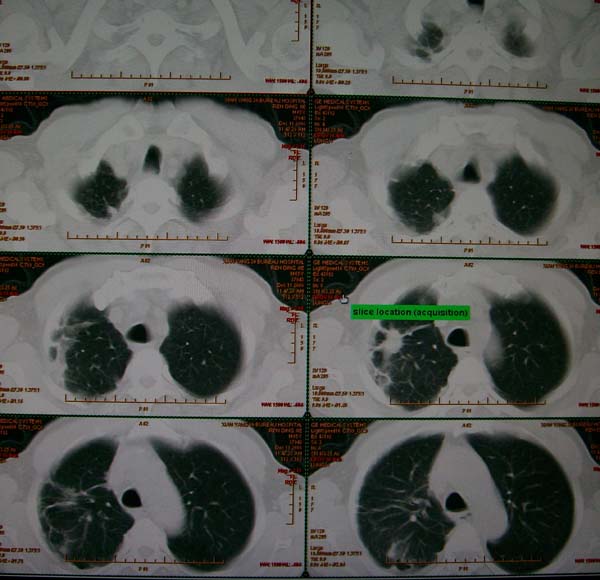

标题: CT17173:M65Y,咳嗽一月。请会诊 [打印本页]

标题: CT17173:M65Y,咳嗽一月。请会诊

右肺多发病灶,右上肺及下肺背段均有灶,考虑结核,

高度提示恶性病变(叶间裂及胸膜下可见结节),多原发或继发.建议高分辨及强化扫描.